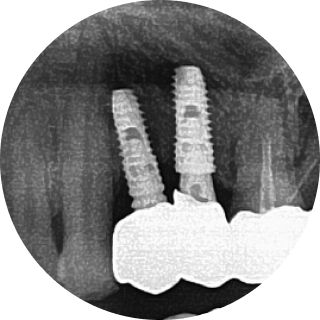

아날로그 치료 잘못된 예

이로운치과의 문제 예방이로운치과의 문제 예방이로운치과의 문제 예방이로운치과의 문제 예방

잘 못 심은 임플란트의 예시입니다.

이로운 치과는 디지털 진료를 통해 정확한 임플란트 식립 위치를 파악하여

아날로그 치료에서 발생할 수 있는 문제를 예방합니다.